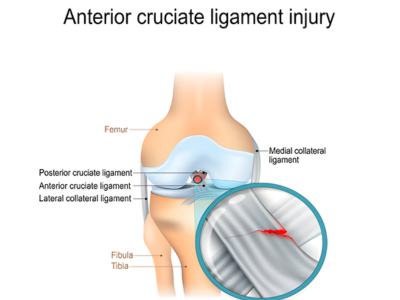

Sports Injuries

Conservative as well as surgical treatments for various sports injuries including ligament tears such as PCL/ACL, tendon injuries and muscle strains.

Ligament or tendon injuries

Specialized treatment to restore function and stability after soft tissue injuries.